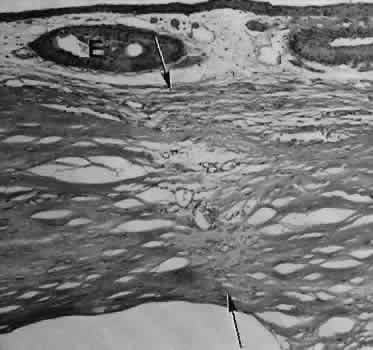

SCLERAL HEALING

The sclera itself does not participate directly in wound healing. Partial-thickness injuries are healed by formation of granulation tissue from the epi-scleral tissue in external wounds or from uveal tissue in internal wounds (Fig. 8). Full-thickness defects of the sclera heal by granulation tissue originating in the episcleral tissue and uveal tract. Mitomycin is used in filtering procedures specifically to prevent the formation of granulation tissue and promote establishment of an aqueous fistula.30

Fig. 8. Following a scleral incision, granulation tissue from episcleral tissue (E) and uveal tissue (U) will proliferate through the full extent of the sclera. The tissue will remodel along tension lines to reapproximate the tensile strength of the original tissue (Hematoxylin-eosin stain; × 28.)

SURGICAL LIMBUS HEALING

Currently, there is a trend for the site of the cataract wound to shift from the limbus to the peripheral cornea31 to reduce induced astigmatism32 and to shorten the natural history of cataract wound healing.33 The healing of the wound is similar to that found in central corneal incisions.

Healing at the site of a limbal surgical incision involves a combination of the features of repair of the cornea, conjunctiva, and sclera (see Fig. 5). Conjunctival epithelium will heal over an area of granulation tissue originating from the substantia propria of the conjunctiva and the episclera. The granulation tissue seals the wound if the wound edges are well apposed. The remainder of the healing process is similar to the healing of an external scleral wound. Granulation tissue is not formed in the internal portion of the wound because the uveal tract is not involved. The internal wound is healed by endothelial migration and reformation of Descemet's membrane in a manner outlined above for full-thickness corneal wounds.34,35

Because of the lack of blood vessels, the rate of wound healing is slow relative to that of the skin. Whereas an injury to the skin may have regained its tensile strength in 7 to 10 days, injuries to the surgical limbus may require as long as 12 months to regain a stable tensile strength. The tissues of the wound remain structurally weaker than the surrounding uninjured tissue (Fig. 9). The healing of a clear corneal cataract incision proceeds as described above.

Fig. 9. A. Well-healed scar (between arrows) barely perceptible in photomicrograph. B. Higher magnification of scar. Migrating corneal endothelium has closed the posterior hiatus of the wound in Descemet's membrane (arrow). (Hematoxylin-eosin stain; A, × 33; B, × 82.)